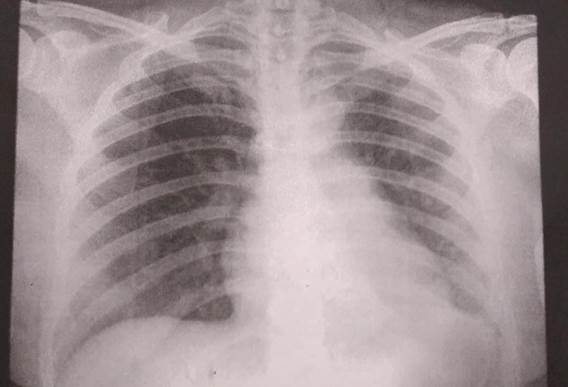

Para el estudio etiológico, se solicitó radiografía de tórax que mostró arteria pulmonar prominente, fondo de saco costo diafragmático izquierdo borrado, doble contorno con sospecha de atelectasia lobar inferior izquierda. Figura 2.